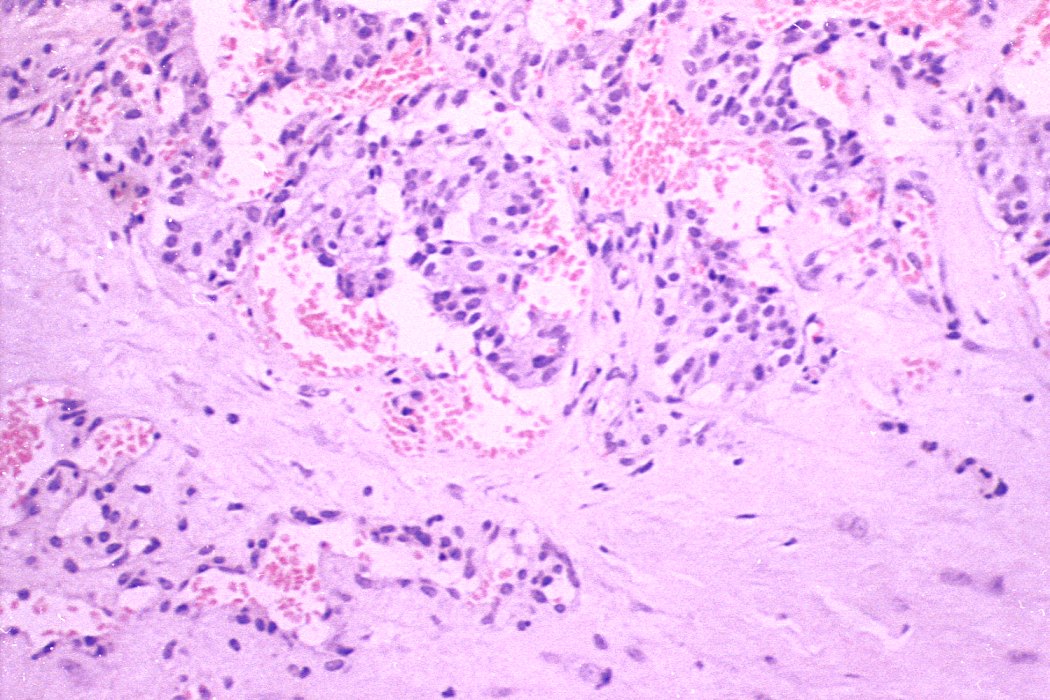

Medullary cancer - Case 5. (histological picture 3)

H.E.-section, 200x. Polypoid tumorous growth is present in the lumen of the centrally located blood vessel.